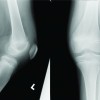

TB of joints typically involves weight bearing joints. Diagnosis of TB is missed due to its nonspecific presentation and atypical findings. A patient with long standing monoarticular involvement of knee should be suspected to be of tuberculous origin to avoid misdiagnosing patients with similar clinico-radiological characteristics, such as PVNS. Diagnosis of tuberculous arthritis at early stage is required to preserve the joint function. Early confirmation of diagnosis, specific and required treatment can have good prognosis [6]. In the early stages, there is inflamed synovium with oedema, initially, clinically there is joint swelling, muscle spasm, and decreased range of motion. An misdiagnosis may be due to nonspecific presentation, nonspecific diagnostic tools, empirical use of antibiotics, and most important of all, the clinician not including tuberculous arthritis in differential diagnosis due to its rare incidence . A study of patients with TB arthritis of knee, preoperatively diagnosed with examination, radiological investigations, and PCR assay, found that only 20% had correctly been diagnosed at the time of admission. Whereas remaining 80% were preoperatively misdiagnosed with gout, rheumatic or osteoarthritis [3]. The patient mentioned here was suspected of PVNS due to the clinical presentation, x-ray, and MRI characteristics. Both tuberculous knee arthritis and PVNS in young present with monoarticular involvement with long standing painful swelling and limited ROM.(Fig. 1).

The MRI features of PVNS include joint effusion, marrow oedema, nodular proliferation of synovial membrane and articular cartilage destruction(Fig. 2). Clustering of deposits of hemosiderin show hypointensity on T1 and T2 weighted images which signifies PVNS. MRI plays an important role in making the diagnosis of PVNS [7]. A biopsy is needed for confirming the diagnosis of TB knee or PVNS. A definitive diagnosis of tuberculous involvement depends on culture findings (80% positive rate) [4,8]; But culture requires a long duration (up to 8 weeks). Thus, the histological finding of proliferative synovium and granuloma (Fig. 3) are taken into consideration for making the diagnosis. The aim of treatment of TB arthritis are to obtain a painless joint, removal of infection and restoring joint function[9], the role of surgery in treating TB arthritis is still controversial. Surgery is reserved for establishing the diagnosis or to treat complications. The surgical indications include nonresponse to AKT after 4 to 5 months of therapy, severe joint involvement, joint destruction and deformity, abscess formation , neurological compromise, and painful ankylosis. The surgical procedures that can be carried out include synovectomy, abscess drainage, and joint fusion and Total Knee Arthroplasty if the TB has remained inactive for a long duration (>/=10 years)[10]. The case discussed above had been advised surgery and intraoperative fibrosis(Fig. 4) was seen at knee joint capsule with destruction of the femoral cartilage. Surgical intervention was planned to achieve better functional outcomes, to detect pathology and have improved ROM at the knee joint with less pain ultimately having good prognosis.